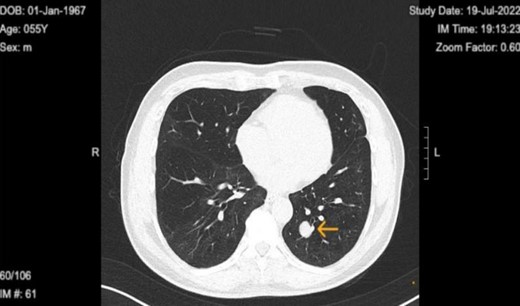

Upon diagnosis of SFT, the patient was referred to a surgeon for consideration for left lower wedge resection via video-assisted thoracoscopic surgery. However, the treatment consisted of monitoring of the tumor with biannual CT scans. Immediate surgical intervention was not performed, as the tumor remained stable in size, asymptomatic, and showed no signs of aggressive behavior. The latest CT on 30 January 2024 shows the tumor size to be 1.9 × 1.6 cm (initial size 1.5 × 1.3 on 21 May 2021) with no accompanying symptoms (Figs 2 and 3).

Chest computed tomography in 2024 shows well circumscribed solitary lung tumor of 1.9 × 1.6 cm in size.

Top image: Coronal view indicating the level of the solitary fibrous tumor (SFT). Bottom image: Axial CT scan at the indicated level, showing a well-circumscribed, homogeneous mass.